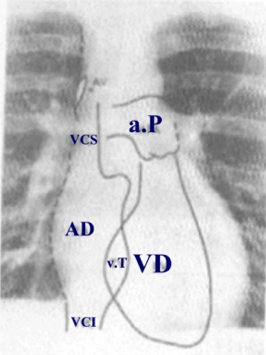

Le camere cardiache nella radiografia del torace in proiezione postero-anteriore (PA) delle camere cardiache sulla radiografia standard del Torace

In proiezione postero-anteriore (quella classica della Radiografia toracica di base) il bordo destro dell'ombra cardiaca e formato da una porzione inferiore, relativamente arrotondata, dovuta all'atrio destro (AD); da una porzione superiore, relativamente rettilinea, dovuta al margine destro della vena cava superiore (VCS) e da una piccola porzione dell’Aorta (AO) ascendente con la vena Azigos

Il BORDO SINISTRO della silouette cardiaca presenta tre archi distinti e precisamente da  due convessità  e una concavità.

Il primo arco, superiore, piccolo e convesso è formato dall’arco aortico.

Il secondo o arco medio, è rappresentato dalla concavità che corrisponde al tronco della polmonare ed alla prima porzione del suo ramo sinistro.

Il terzo o arco inferiore, il maggiore dei tre, è un'altra convessità corrisponde alla parete anteriore e laterale (o libera) del Ventricolo Sinistro (VS). Una accentuazione di questo arco esprime alterazioni del ventricolo sinistro.

All'unione del II con il III arco si trova l'auricola dell'Atrio Sinistro (AS) che normalmente appare indistinguibile.

Come si può notare che, in proiezione standard Postero-Anteriore della radiografia del torace, il Ventricolo Destro (VD) non interviene a delineare alcun profilo dell’ombra cardiaca. Pertanto le alterazioni del Ventricolo Destro si manifestano sul profilo radiografico del cuore solo in maniera indiretta sia attraverso l’arrotondamento del profilo superiore dell’arco medio di sinistra (che rappresenta l’aumento dell’arteria polmonare) sia per l’innalzamento della punta del cuore (apice cardiaco) che rappresenta indirettamente l’aumento del ventricolo destro.